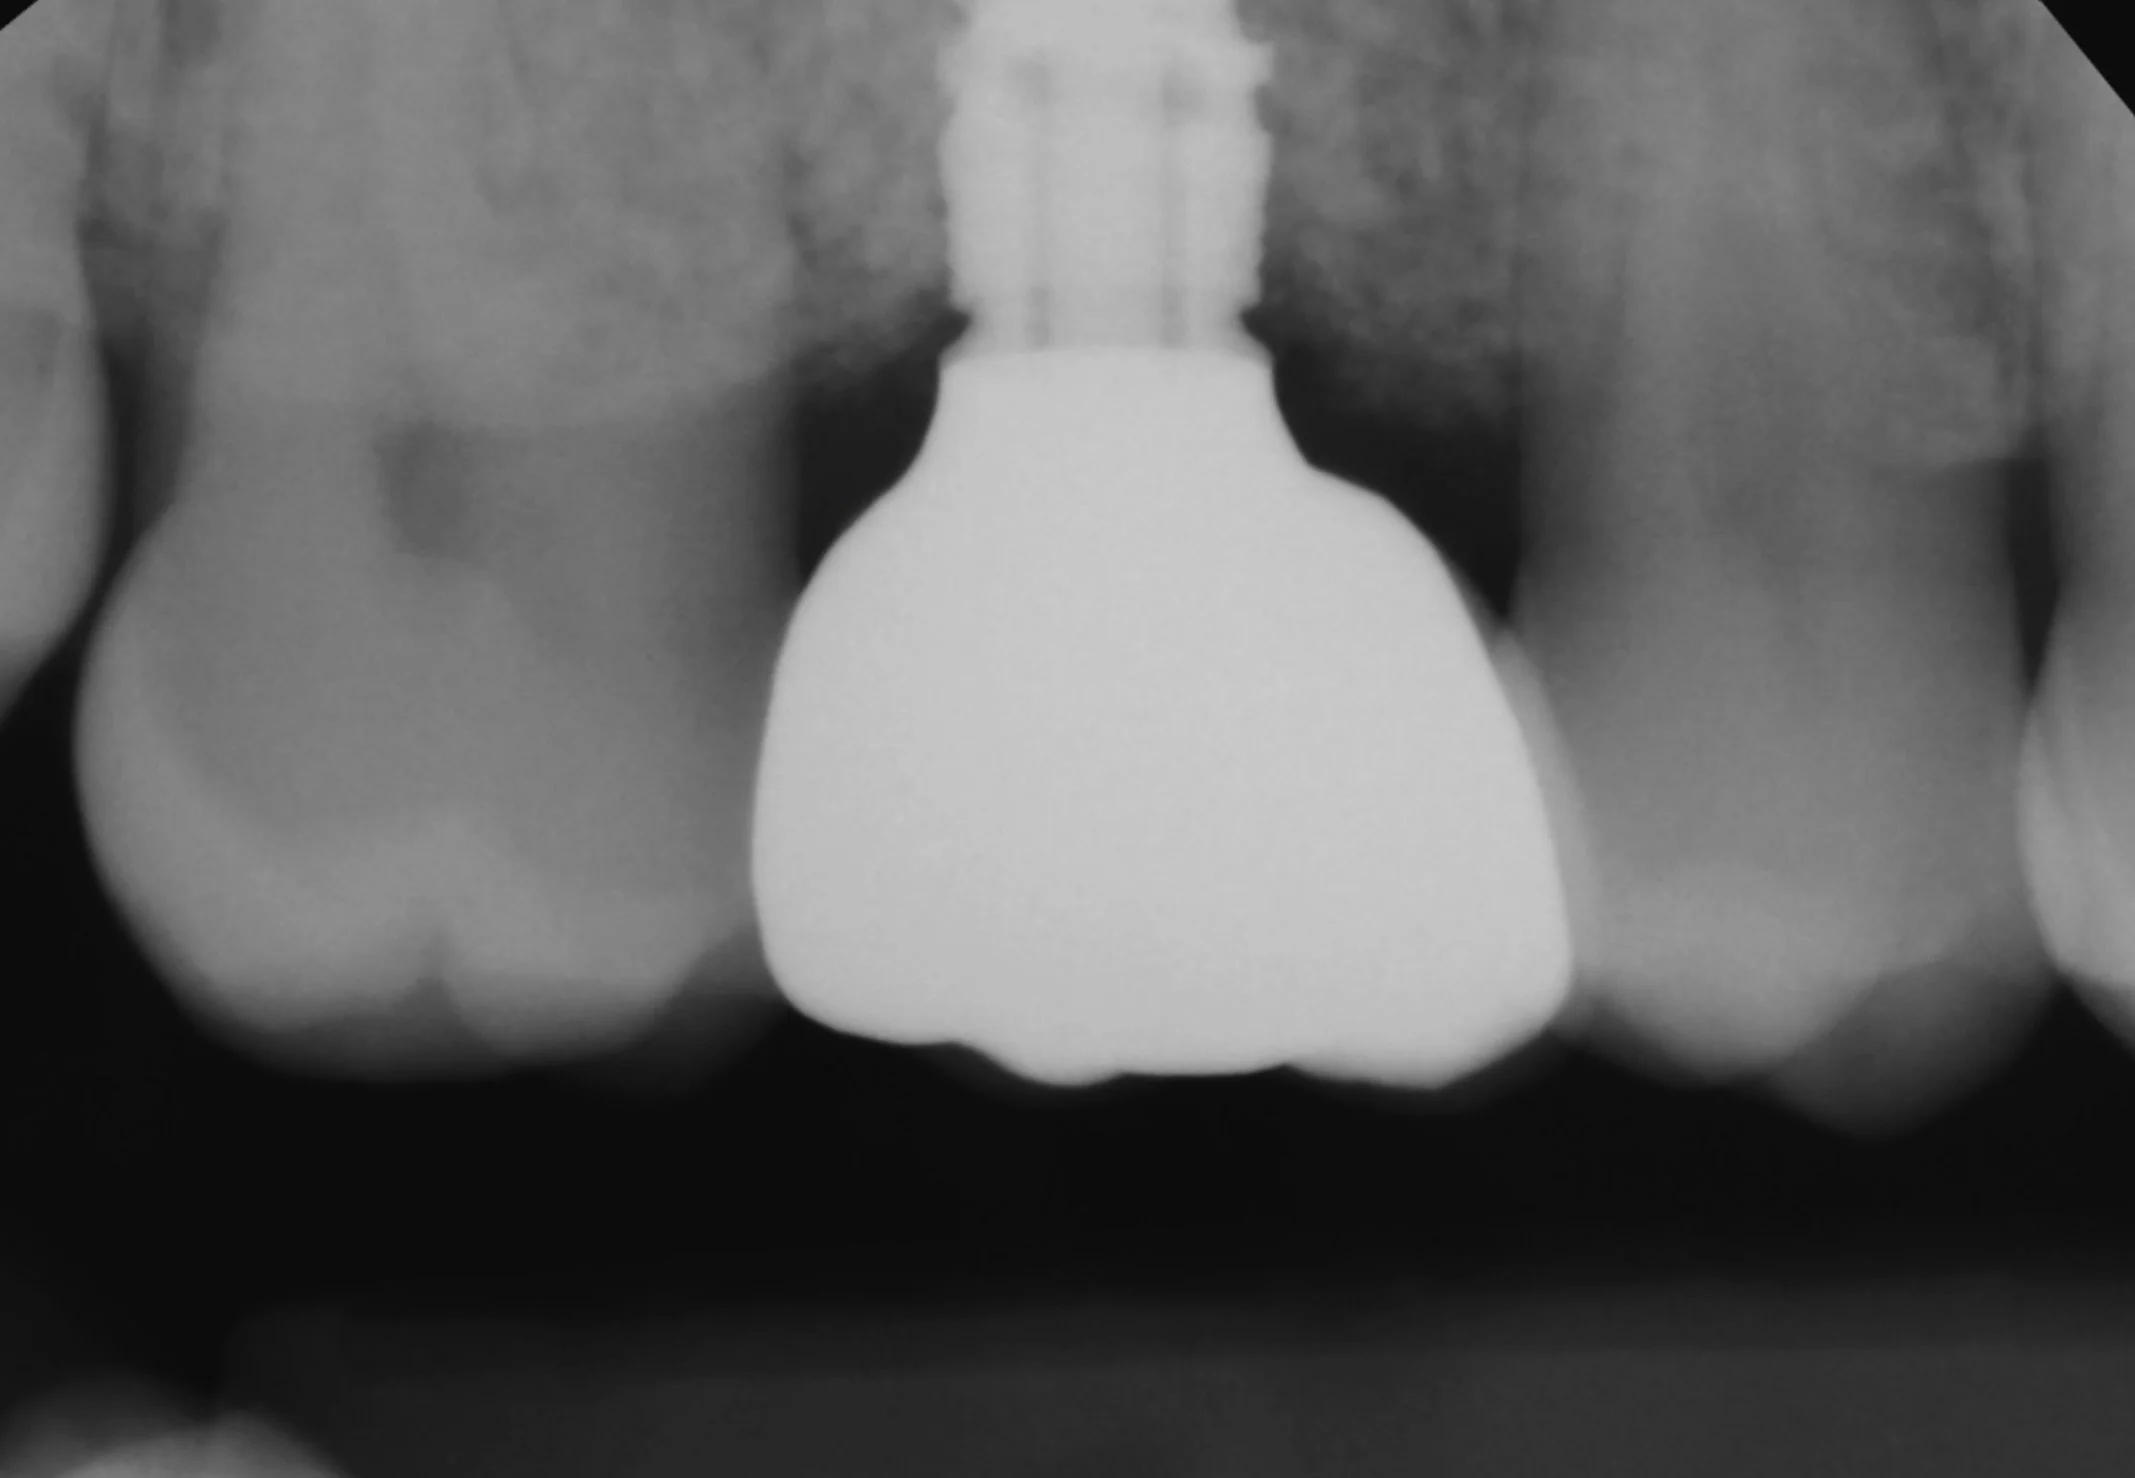

WORKS › 2 Implants + Crowns

2 Implants + Crowns

2 IMPLANTS + 2 CROWNS

Porcelain, Titanium, Allograft, and Xenograft.

Dr. Heldt, 2025. Newport Beach, California.

2 Extractions, 2 Implants placed, 2 Layered Zirconia Crowns over NobelProcera ASC zirconia abutments. Medium-Light translucency. Surgical + Restorative by Dr. Heldt.

Zirconia is the most tissue friendly material for abutments.  The ASC abutment by Nobel Biocare is the Dr. Heldt’s preferred choice not only best for tissue but it also gives the most aesthetic results since the zirconia comes in different shades.

Zirconia is the most tissue friendly material for abutments. The ASC abutment by Nobel Biocare is the Dr. Heldt’s preferred choice not only best for tissue but it also gives the most aesthetic results since the zirconia comes in different shades. Titanium abutments on the other hand are grey and creates a grey hue to crowns.

Titanium connection to the implant with the ASC adapter.  Zirconia material contacts tissue for the best adhesion and aesthetics.